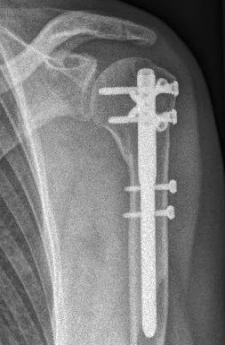

Oberarmschaftbruch3Oberarmschaftbruch4Oberarmschaftbruch5

Picture: An upper arm shaft fracture can alternatively be stabilized by a plate that bridges the fracture. The picture shows a shaft fracture with a bending wedge. After surgical treatment, the upper arm shaft is back in the correct axis.